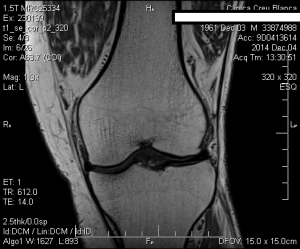

La mejoría sintomática fué casi inmediata y la evolución se hizo evidente en la RM el 4/12/2014, en menos de dos meses de realizado el tratamiento con implantes de oro. El paciente tenía unas perspectivas (según los médicos tratantes) de una baja laboral de muchos meses, con una gran incertidumbre respecto a su futuro laboral, y con un pronóstico incierto de su capacidad laboral.

A continuacion se observan las imágenes más significativas: